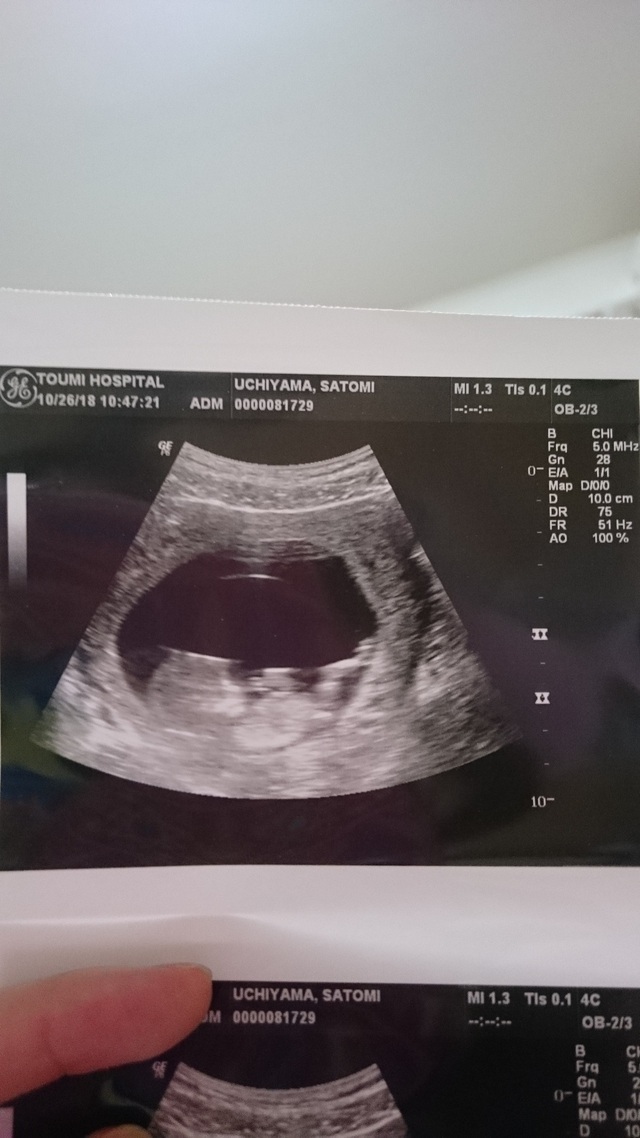

11週0日(11w0d・女の子)|pon2019610 さん(28歳)

エコー写真撮影時のエピソード:

妊娠が分かった産婦人科ではお産ができないため、紹介された産院で初めてのエコーでした。

前回も前々回も流産しており、不安な気持ちいっぱいで産院に向かってしてもらったエコー。

私の不安をよそに、まるで私を安心させるようにいっぱい動いてくれた赤ちゃん。エコーをする先生も笑っておられました。

あまりに動き回るものだから写真におさめるタイミングも大変だったみたいで、いただいた写真を改めて見返すと、きっとぶれてしまったんだと思いますが、まるでくちばしがはえているかのように見える写真が!

おもわず主人と笑ってしまいました(笑)

私の家族に見せると、くちばしあるやん!くちばしっち(たまごっちのキャラ)や!と(笑)

おかげでそのときからお腹の子は『くっちー』と呼ばれています(笑)

産まれてからも私の家族からの呼び名がくっちーのままだったらどうしよう?と今から心配です(笑)